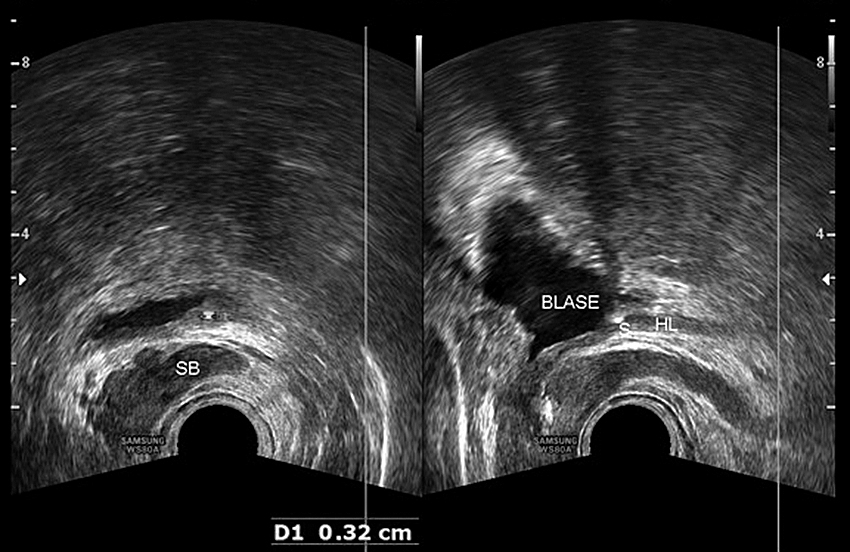

Bei den distal-prävesikalen Steinen hat der transrektale Ultraschall schon längere Zeit seine Bedeutung gefunden, allerdings nur bei wenigen Untersuchern. Bei Frauen eignet sich dazu der transvaginale Schall, der den Harnleiter bis zur Gefäßkreuzung verfolgen und den erweiterten Harnleiter komplett mit dem transabdominalen Schall auf eine Steinobstruktion untersuchen lässt. In der gynäkologischen Abteilung steht mir seit 2/2017 ein high-end-Sonogerät der Fa. Samsung WS80A zur Verfügung.

Bei den 295 stationären Patienten mit Nierenkoliken hatten 111 Patienten einen proximalen Stein, bei 184 Patienten wurde der Stein distal der Gefäßkreuzung gesichert. Bei den prävesikalen Steinen konnte in der transrektalen Sonographie der Stein bei den Männern in den letzten 3,5 cm sicher gesehen, in der vaginalen Sonographie der Harnleiter mit dem Stein teilweise bis zu den iliakalen Gefäßen verfolgt werden.

Bei den 111 Patienten mit proximalen Steinen konnten die Steine bei 102 Patienten (92 %) auch im Ultraschall gesehen werden. Bei 59 Patienten (53 %) war für die Steinsicherung kein CT angefordert worden. Bei den 184 Patienten mit distalen Harnleitersteinen wurde der Stein bei 171 Fällen (93 %) in der transrektalen/transvaginalen Sonographie verifiziert, bei 123 Patienten (66 %) wurde auf eine CT-US verzichtet. Fornixrupturen konnten bei den letzten 50 Patienten zu 22 % durch high-end-Geräte gesehen werden, immer ohne klinische Konsequenz; bei 6 Patienten wurde bei der Aufnahmeuntersuchung eine Urosepsis erkannt und durch die alleinige sonographische Steinsichtung rasch einer endoskopischen Steinsanierung zugeführt.

Der Ultraschall kann sehr erfolgreich in der Steinfindung bei Nierenkoliken mit Erweiterung des oberen Harntraktes eingesetzt werden. Intensivpflichtige Patienten können dadurch ohne aufwendigere CT-Untersuchung rasch einer Diagnostik und entsprechender Steinsanierung zugeführt werden. Steinabgänge v. a. bei distalen/prävesikalen Steinen können in der ambulanten Nachsorge durch den transrektalen oder transvaginalen Schall gesichert werden.